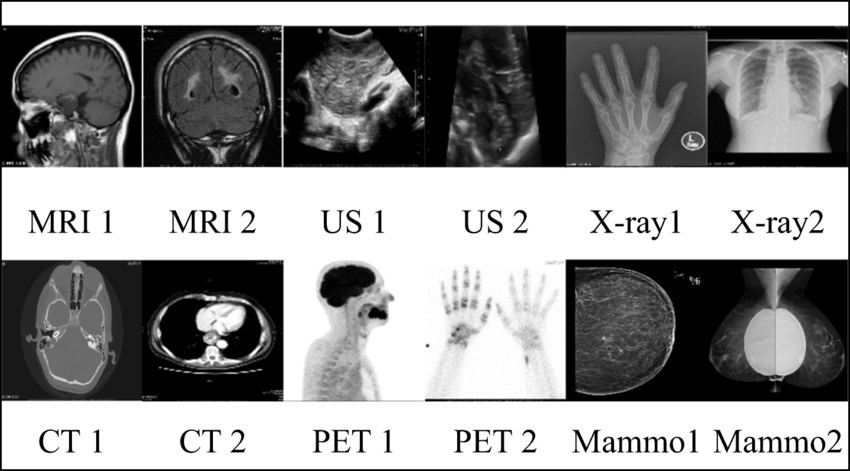

radiographic appearance description

attenuation

radiographs: radiolucent, semi-radiopaque, radiopaque

MRI: void, intermediate signal intensity, high signal intensitiy

ultrasound: anechoic (black), hypoechoic, hyperechoic (bright)